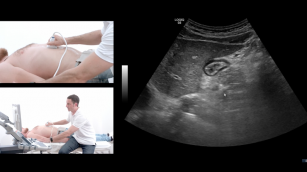

How to identify ascites on an ultrasound. 6th Dec 2017 - Sara Damewood, MD Learn how to distinguish between free fluid and abdominal structures on an ultrasound image.